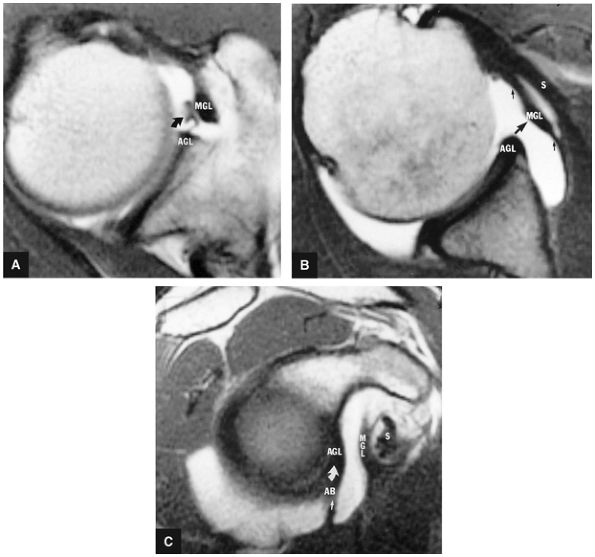

FIGURE 8.83 ● T2*-weighted axial images at (A) and below (B) the level of the subscapularis show the normal middle glenohumeral ligament (MGL; curved arrows), its medial origin from the glenoid and neck of the scapula, and its attachment to the lesser tuberosity. Small straight arrows, anterior labrum. (C) A T1-weighted sagittal oblique arthrogram shows the attachment of the MGL (mgl) to the anterior superior glenoid labrum (asl). The MGL arises from the labrum below the superior glenohumeral ligament and from the neck of the scapula. The humeral attachment of the MGL is located medial to the lesser tuberosity. Normal variants of the MGL include the ligament arising only from the labrum or having no attachment to it. pb, posterior band of IGL; s, supraspinatus tendon. (D) Arthroscopic view of the middle glenohumeral ligament (MGL) anterior to the anterior labrum (AL) and posterior to the subscapularis tendon (Sub). An anterior superior quadrant sublabral foramen (curved arrow) exists as a normal variant. HH, humeral head.

of the shoulder joint from 0° to 45° of abduction.59 Along with the subscapularis tendon and the superior part of the IGHL, the MGHL contributes to anterior stability at 45° of abduction.64 In the lower and middle ranges of abduction, the MGHL limits external rotation. The MGHL has also been shown to have a secondary role in anterior stability of the shoulder in 90° of abduction when the anterior band of the IGHL is cut.65 Inferior translation of the abducted and externally rotated shoulder is limited as a secondary restraint function of the MGHL. With internal rotation the MGHL demonstrates a more vertical orientation, and with external rotation it assumes a more horizontal orientation (elongation of the MGHL).